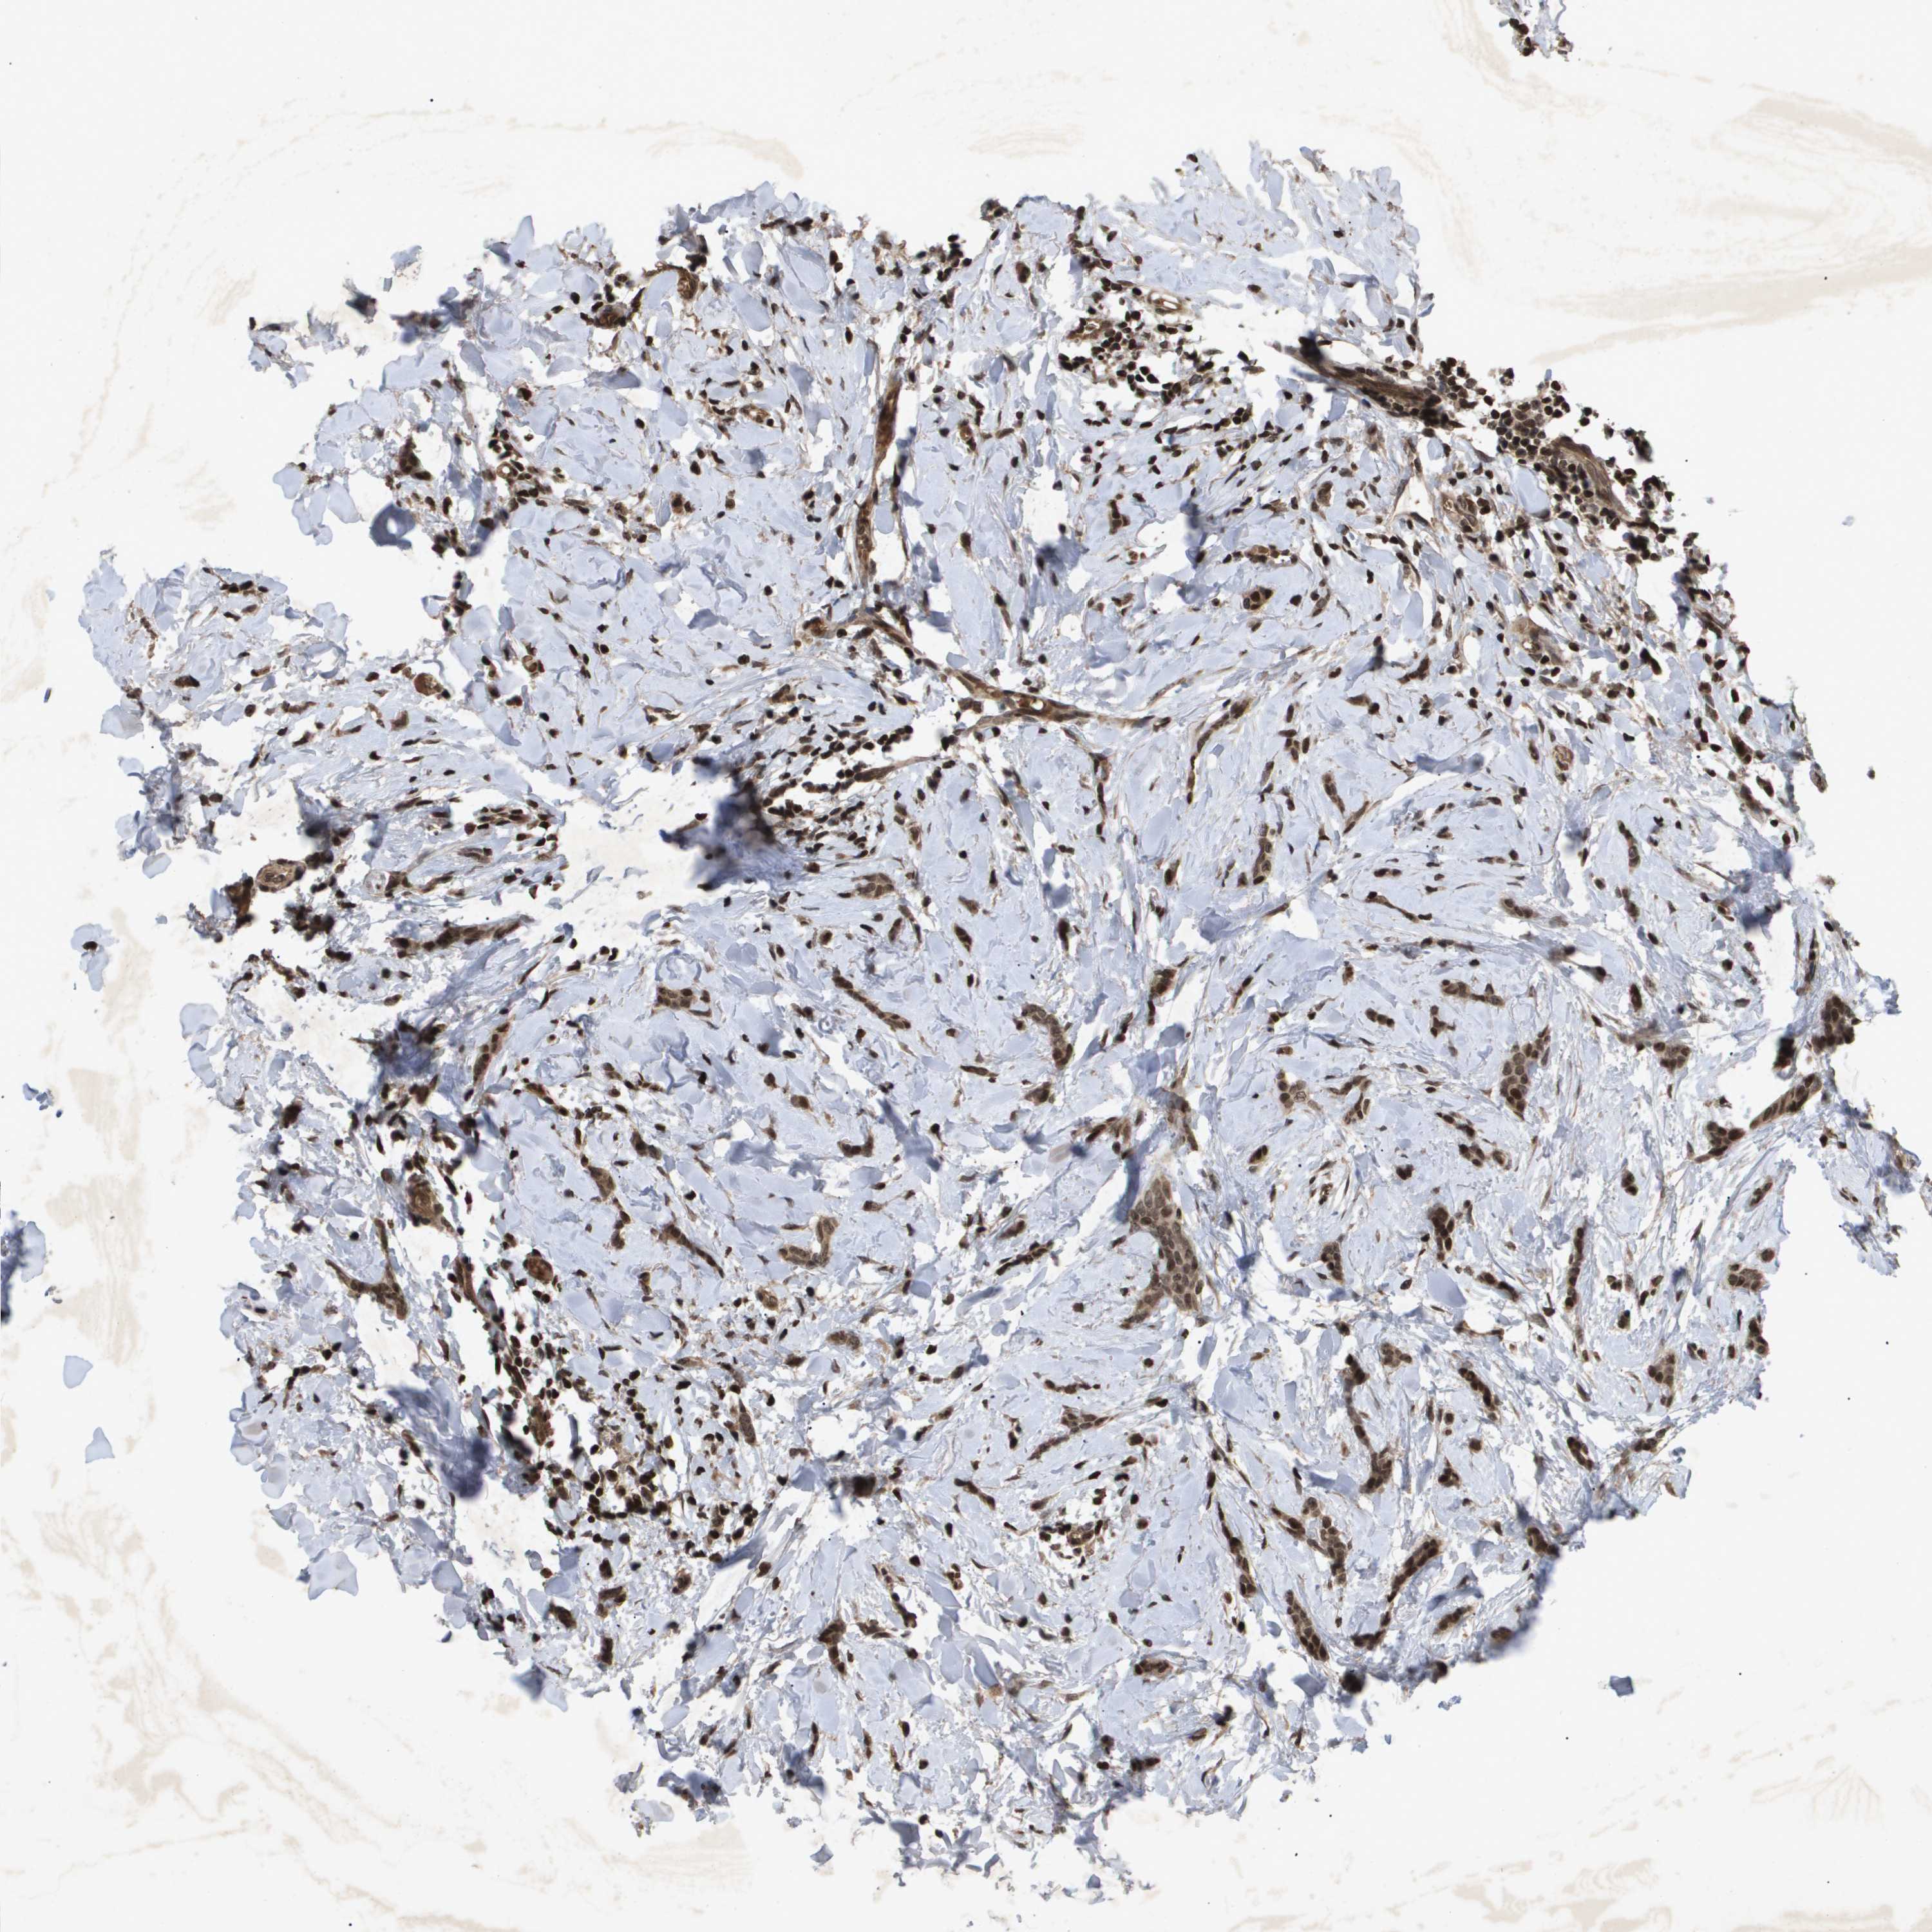

CANCER BREAST CANCER Show tissue menu

BRCA TCGA BRCA VALIDATION PROTEIN EXPRESSION

ANTIBODIES

AND

VALIDATION